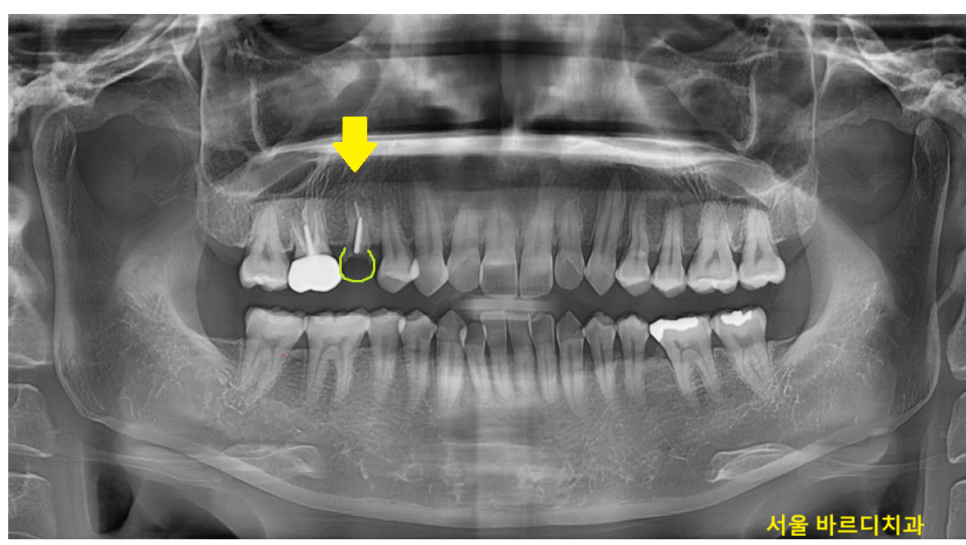

x-ray를 찍어 확인해보니 신경치료도 되어있고

우식이 심했었는지

치아에 기둥까지 박혀있습니다.

씌운 치아 부러짐이 발생한 것인데..